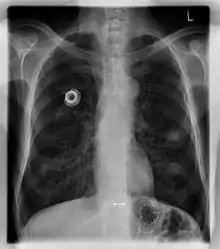

صورة أشعة للصدر تظهر القسطر المغروس.